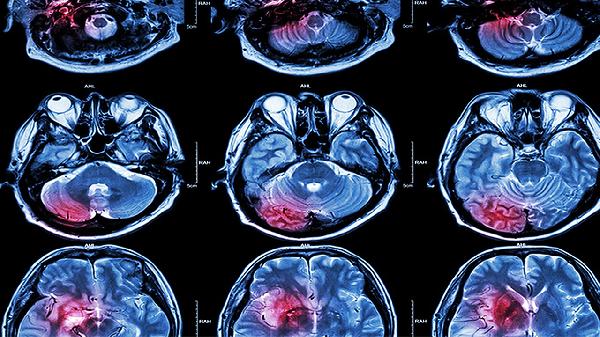

脑外伤后遗症可通过药物治疗、康复训练、心理干预、物理治疗和手术治疗等方式改善。脑外伤后遗症可能与脑组织损伤、神经功能缺损、颅内压增高、脑脊液循环障碍和脑代谢异常等因素有关,通常表现为头痛、眩晕、认知障碍、肢体无力和情绪波动等症状。